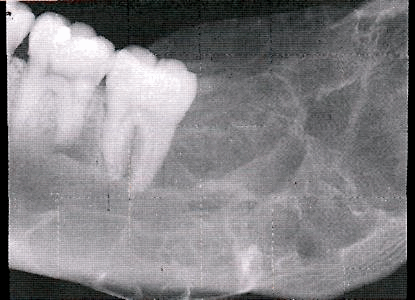

Амелобластома - наиболее частая одонтогенная опухоль челюстей, склонная к инвазивному, местно-деструирующему росту. Поражает преимущественно нижнюю челюсть в области ее тела, угла или ветви. Развивается внутрикостно, может прорастать в мягкие ткани дна полости рта и десны. Чаще проявляется в возрасте 20-40 лет.

В начальном периоде амелобластома протекает бессимптомно, однако по мере увеличения размеров опухоли возникает деформация челюсти, асимметрия лица. Зубы в области поражения часто становятся подвижными и смещаются, может отмечаться зубная боль. Опухоль верхней челюсти может прорастать в полость носа, гайморову пазуху, орбиту; деформировать твердое нёбо и альвеолярный отросток. Нередки случаи нагноения, рецидивирования и малигнизации амелобластомы. Клиническое течение таких опухолей челюсти, как амелобластическая фиброма и одонтоамелобластома, напоминает амелобластому.

Рентгенологическая картина. Фиброма проявляется в виде гомогенного разряжения костной ткани округлой формы с относительно четкими границами. Патологический очаг окаймлен истонченным слоем кости без периостальной реакции. В центре очага могут быть участки петрификации.

Рентгенологическая картина. Определяется очаг деструкции костной ткани с нечеткими границами. В некоторых случаях может иметь вид мелких ячеистых образований, разделенных костными перегородками.

Рентгенологическая картина опухолевых поражений челюстных костей немногочисленна, это деструкция, деформация кости и периостальная реакция. Деструкция наблюдается в виде одиночного (фиброма, миксома, энхондрома, остеобластокластома, остеогенная саркома и др.) и множественных очагов (эозинофильная гранулёма, полиоссальная фиброзная дисплазия). Форма очагов деструкции может быть округлая, продолговатая, неправильная, очаги деструкции могут локализоваться в любом участке кости челюсти, располагаясь центрально или периферически.